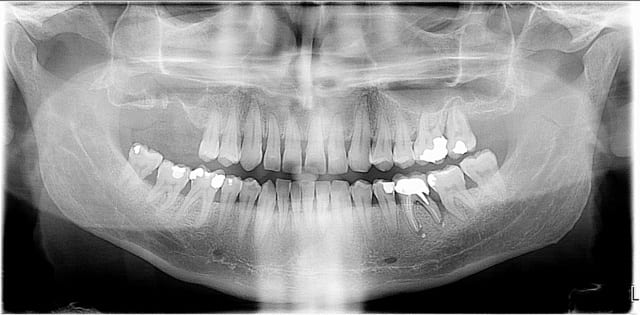

je souhaiterais qq avis sur le traitment de ce patient qui est fumeur svp

j'ai proposé au patient ttt paro curetage-surfaçage (j'ai commencé les séances)

_concernant le remplacement de 16 et 17 le patient se voit mal supporter de l'amovible et serait prêt à faire sinus- lift + greffe d'apposition + implants(en se calmant sur la clope...).

_concernant la 36 qui est à extraire à mon avis (ne me parlez pas d'amputation radiculaire svp... lol) pensez vous qu'un bridge couronne sur 35 vivante et onlay sur 37 serait possible mécaniquement , en alternative à l'implant ? Avez vous déjà réalisé ce type de bridge et si oui seule la zircone est utilisable ?

j'ai bien sur expliqué au patient que le remplacement de 26 et 27 sera bientôt d'actualité...

A la base j'avais fait un devis pr stellite 4 dents haut (la 26 et la 27 sont en bout de course avec mobilité grade 2 sur 26 et 3 sur 27) et bridge CM 35 à 37 mais le patient s'est dit prêt à se calmer sur la clope pour avoir des implants.

Pour les questions sur le bridge c'est surtout pour avoir votre avis sur ce type de bridge avec onlay comme ancrage: Est-ce assez costaud pour remplacer une molaire ? Est-ce possible de réaliser ce type de bridge en céramo-métallique (même au niveau de l'onlay) ?